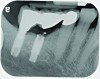

Implant related complications may be classified as minor, intermediate, major reversible/nonreversible, or major nonreversible. For example, a simple complication like a fractured abutment screw is usually considered a minor complication. It usually can be corrected with minimal cost, time, pain, and inconvenience. Treatment may be more involved for an intermediate complication such as a fractured implant (Figure 1). Up the severity scale are major complications, such as when an implant migrates into the sinus2 (Figure 2), or is exposed by mucosa and bone loss and visible to the patient a year after restoration (Figure 3 and Figure 4). Major complications may cause irreversible damage and/or require multiple procedures to try to make the patient “whole,” adding cost, time, pain, and surgeries (Figure 5 and Figure 6), and the patient may or may not receive the original restoration.

A fractured implant is classified as an intermediate complication

Figure 1